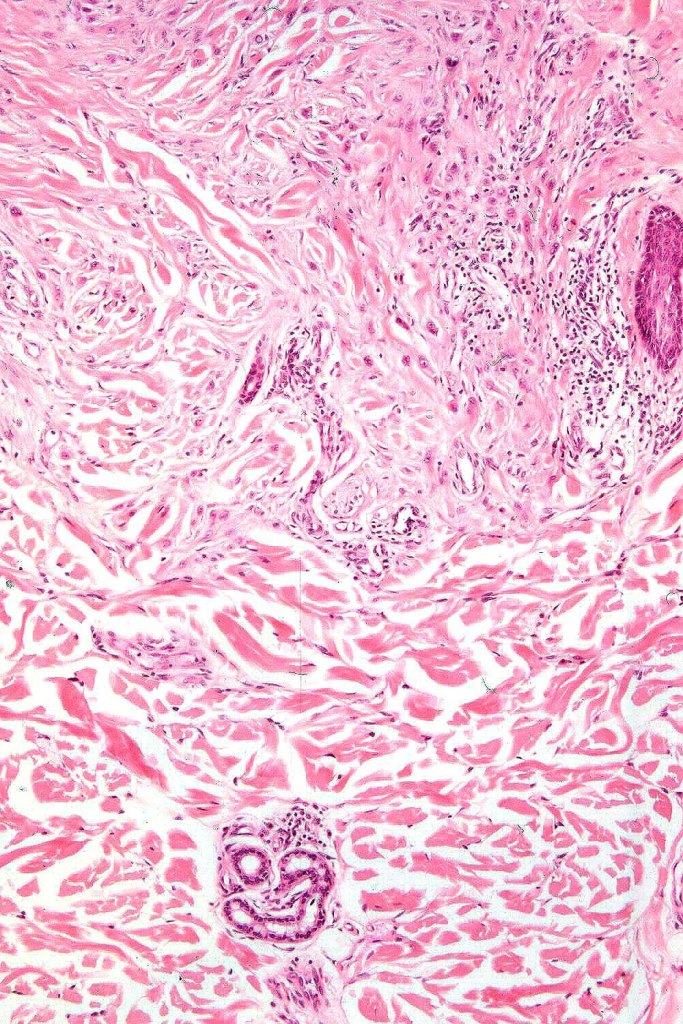

•For the most part, the lesion is composed of somewhat pleomorphic, spindled or epithelioid cells with often abundant eosinophilic cytoplasm & vesicular nuclei with small nucleoli. Melanin is either sparse or absent

•Intranuclear cytoplasmic pseudoinclusions are generally present

•With increasing depth (or age of the lesion), the nevus cells are separated by a dense, sclerotic stroma

•Mitoses are either absent or ocassionally 1 or at most 2 may be seen